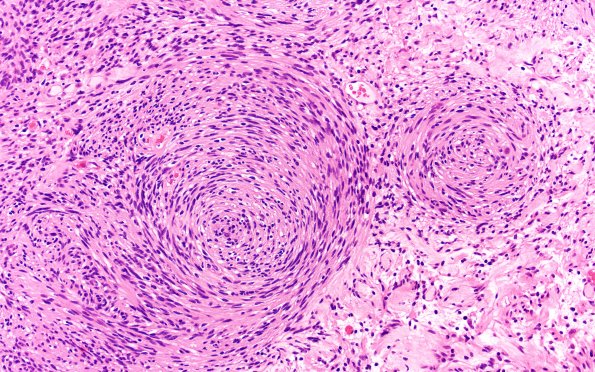

Washington University Experience | NEOPLASMS - CRANIAL AND PARASPINAL NERVEs | Schwannoma | 31A3 Schwannoma, whorled NF2 (Case 31) H&E 20X

H&E-stained sections show a well-circumscribed cellular, spindle cell tumor with large lobular whorl formation, thick-walled vessels, lobular whorls, and cystic spaces with pseudo-epithelial lining. (H&E)